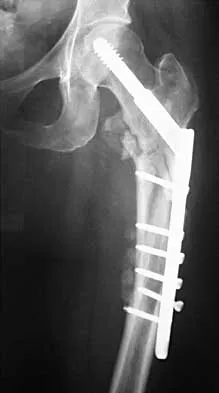

Figures 7a and 7b show the radiographs of a 51-year-old woman who injured her left leg after falling off a stepladder. Surgical reconstruction is performed with a compression screw and side plate; the postoperative radiograph is shown in Figure 7c. Following gradual progression of weight bearing, she reports that she slipped again and placed full weight on the extremity. She now notes a new onset of increased pain in her left thigh and hip region. Follow-up radiographs are shown in Figures 7d and 7e. Reconstruction should consist of

The initial fracture was an unstable reverse oblique intertrochanteric fracture with subtrochanteric extension. Initial fixation with a high-angled screw and side plate construct may not provide stability as well as a 95 degree fixed-angle device or a intramedullary hip screw device. The follow-up radiographs show loss of fixation and further propagation of the fracture distally. Reconstruction would best be accomplished with hardware removal and conversion to a long intramedullary nail with femoral head fixation or a 95 degree angled plate and screw device. Conversion to a longer plate does not improve the biomechanical situation at the primary fracture site. In situ bone grafting would not provide any additional stability and would not correct the deformity. The proximal femoral fracture is not amenable to retrograde nailing. Cerclage wiring will not sufficiently enhance stability and is not indicated. Bridle SH, Patel AD, Bircher M, Calvert PT: Fixation of intertrochanteric fractures of the femur: A randomized prospective comparison of a gamma nail and dynamic hip screw. J Bone Joint Surg Br 1991;73:330-334. DeLee JC: Fractures and dislocations of the hip, in Rockwood CA Jr, Green DP, Bucholz RW, Heckman JD (eds): Rockwood and Green's Fractures in Adults, ed 4. Philadelphia, PA, Lippincott-Raven, 1996, pp 1659-1825. Haidukewych GJ, Israel TA, Berry DJ: Reverse obliquity fractures of the intertrochanteric region of the femur. J Bone Joint Surg Am 2001;83:643-650.